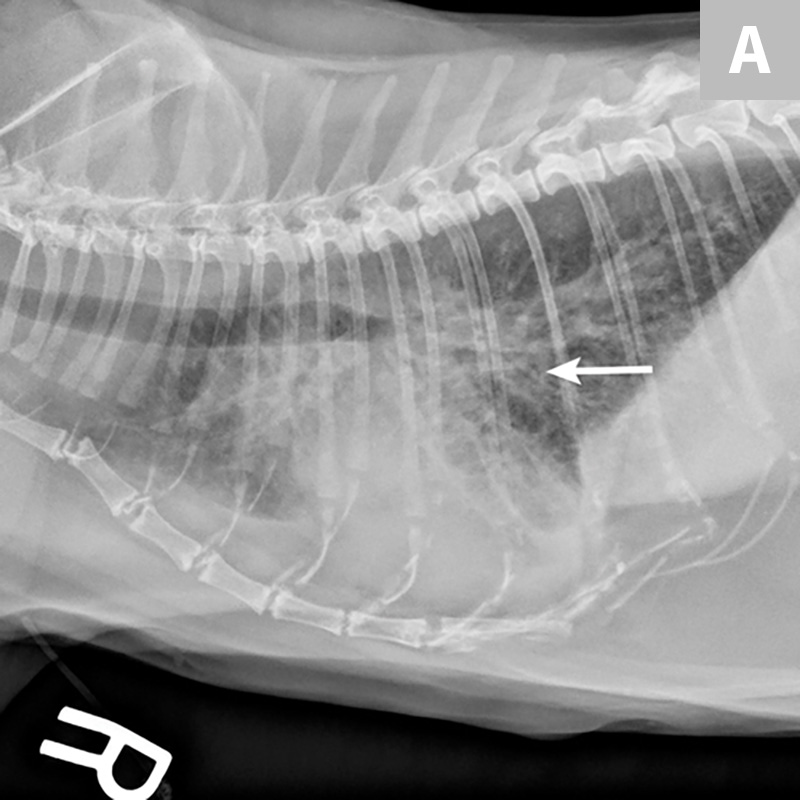

Figure 3 from Radiographic abnormalities in cats with feline bronchial disease and intra and What Causes Feline Lung Disease Here's how to differentiate between the 2 in cats. “the three most common causes of respiratory distress,” says dr. Feline respiratory disease complex is typically manifested by clinical signs of the eyes, nose, and mouth (rhinosinusitis, sneezing, conjunctivitis,. Lower airway disease is classified into 2 predominant categories: Major categories of feline respiratory disease include the following:• infectious: Rhinitis, tracheobronchitis, and. What Causes Feline Lung Disease.